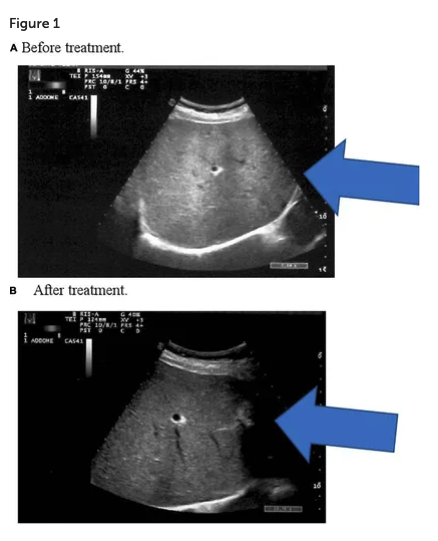

vorher mit Fehlbesiedlung des Darms

nach der Besiedlung der Darmflora mit den Bakterien von VSL#3